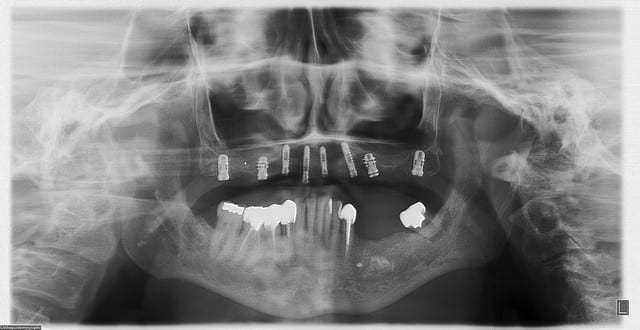

allez, dans ma série, "je remets des sujets" je vous donne quelques nouvelles de ce cas

la raison et vos conseils me sont revenus, j'ai posé hier 2 implants supplémentaires en 17 et 27 (sans les facturer à mon patient)

ce qui me frappe, tout de même, avec les quelques radios prises, c'est la cicatrisation osseuse au niveau de ceux en 15 et 25 (cf panos jour de la pose/3mois/4mois et les "zooms" pose/4mois)

la nature est parfois très sympa...;-)